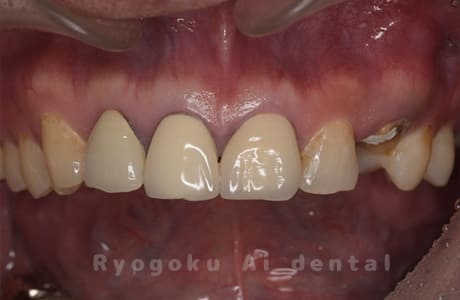

前歯の腫れが治らないとのことでご来院された患者様です。虫歯も大きかったですが、手術を行い、歯牙の保存を行いました。現在も問題なく経過しております。

<リスク・副作用>

過度の咬合や衝撃で割れることがあります。手術後は痛み、腫れ、痺れ、青あざなどの副作用が生じます。痛みは痛み止めを処方しますが、腫れ、青あざは1週間程度生じる場合があります。また、部位によっては神経の走行が複雑で、痺れが残り、長期的にお薬を処方する場合があります。

Case10

-

- 原因

- 重度カリエス

- 治療日数

- 10ヶ月

- 治療内容

- クラウンレングスニング、ポンティックシールド、セラミッククラウン修復

- 治療費用

- 約1,500,000円